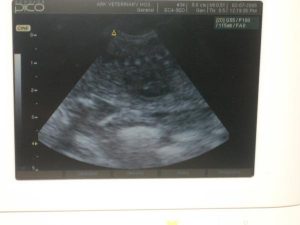

At Ark Veterinary Hospital in Kerrville, TX, we offer state-of-the-art medical technology. One of the diagnostic tools we use is ultrasound, which creates images of the inner workings of the body.

Ultrasound uses sound waves to offer a non-invasive, painless, and radiation-free method of imaging your pet’s internal organs. This is one of the many ways we are dedicated to providing your pet with the best care possible.

By using ultrasound, we have yet another powerful tool at our disposal to detect, diagnose, and prevent illness in your pet.